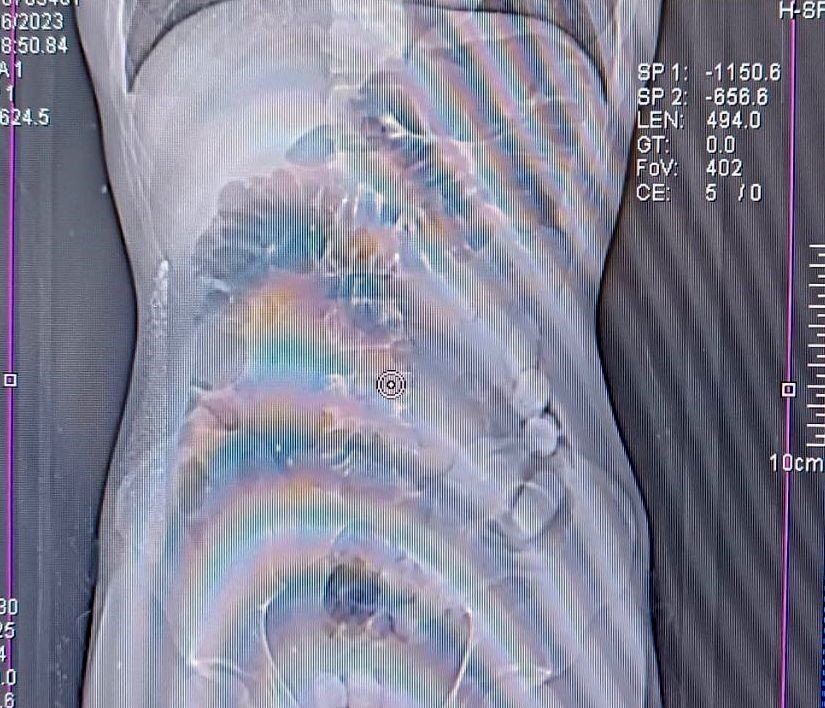

Erzincan ve Diyarbakır Emniyet Müdürlüğü Narkotik Suçlarla Mücadele Şubesi ekiplerinin koordineli çalışması sonucu, uyuşturucu madde kuryeliği yapan kişilere yönelik şehir genelinde çalışma başlatıldı. Bu çerçevede durdurulan yolcu otobüsünde, yutma yöntemiyle uyuşturucu taşıdığı değerlendirilen İran uyruklu M.M.A ve O.A gözaltına alındı. Şüphelilerin mide ve bağırsaklarında yapılan tomografi çekimlerinde çok sayıda yabancı cisim bulunduğu tespit edildi. Yapılan tıbbi müdahale ile şüphelilerin midesinden toplam 1,748 gram uyuşturucu çıkarıldı. Yapılan tıbbi müdahale ile M.M.A'nın midesinden çıkarılan 81 adet 934,96 gram ile O.A'nın midesinden çıkarılan 67 adet 813,07 gram afyon sakızına el konuldu.